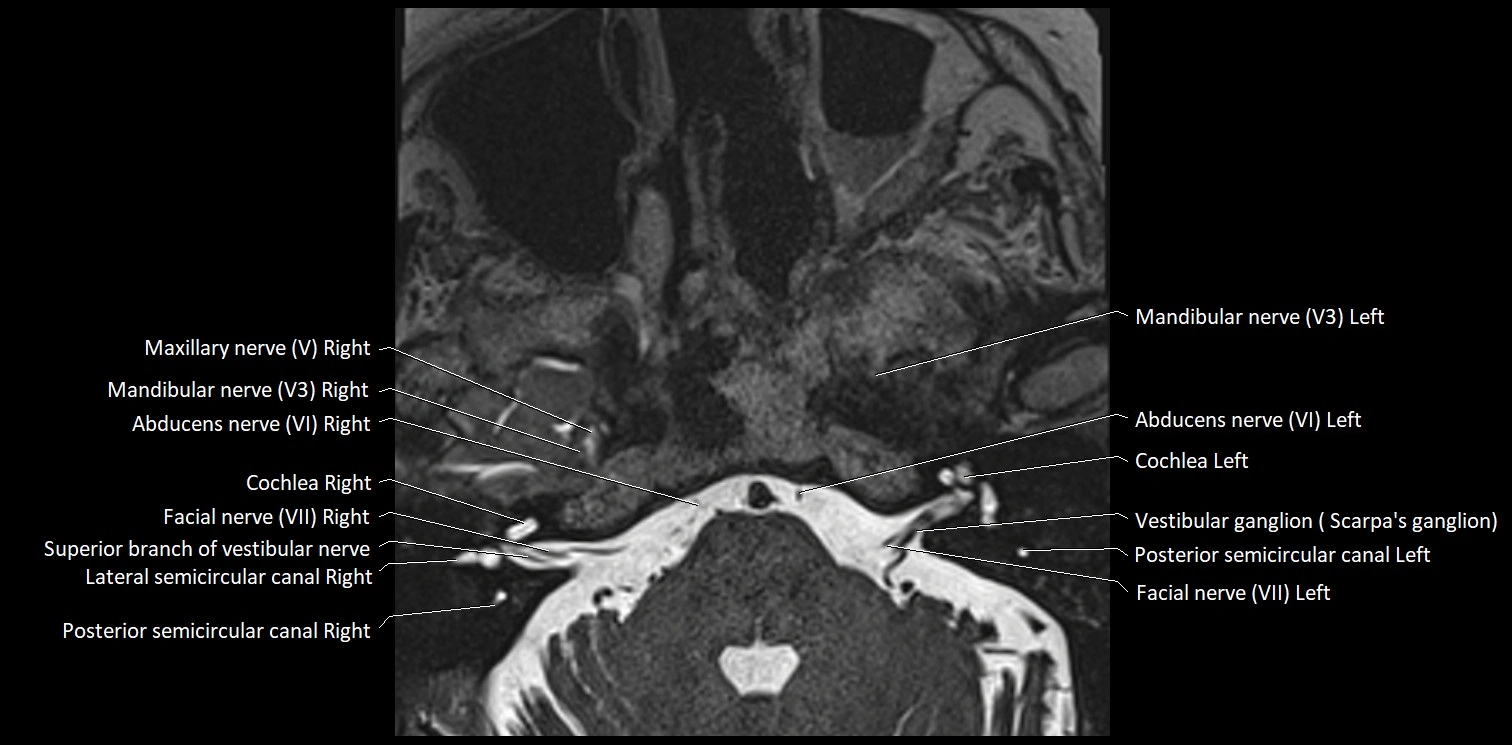

MRI Appearance

• The abducens nerve is a small, thin, linear structure

• Best visualized on high-resolution T2-weighted 3D MRI sequences (e.g., FIESTA or CISS)

• Seen as a hypointense (dark) line running from the brainstem at the pontomedullary junction, traversing the prepontine cistern, and entering Dorello’s canal under the petrosphenoidal ligament, then into the cavernous sinus, and finally the orbit

• May be challenging to visualize in standard MRI due to its small size

• Pathology may be inferred by absence, displacement, or enhancement of the nerve

MRI images

image